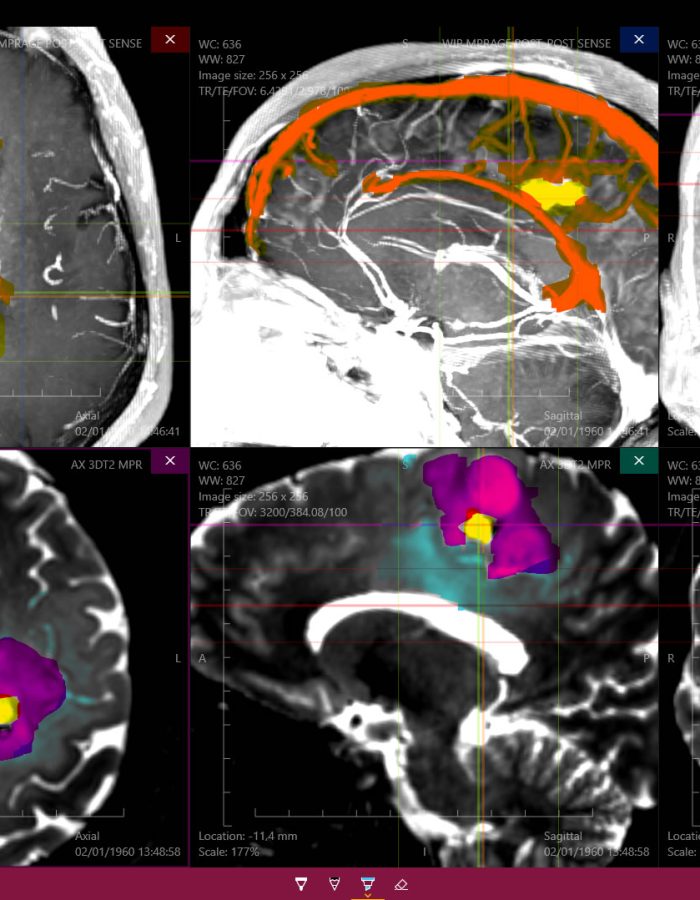

_ Amplia variedad de imágenes con un estilo profesional, tanto para estudios de casos pre operatorios como para estudio profundo de medicina.